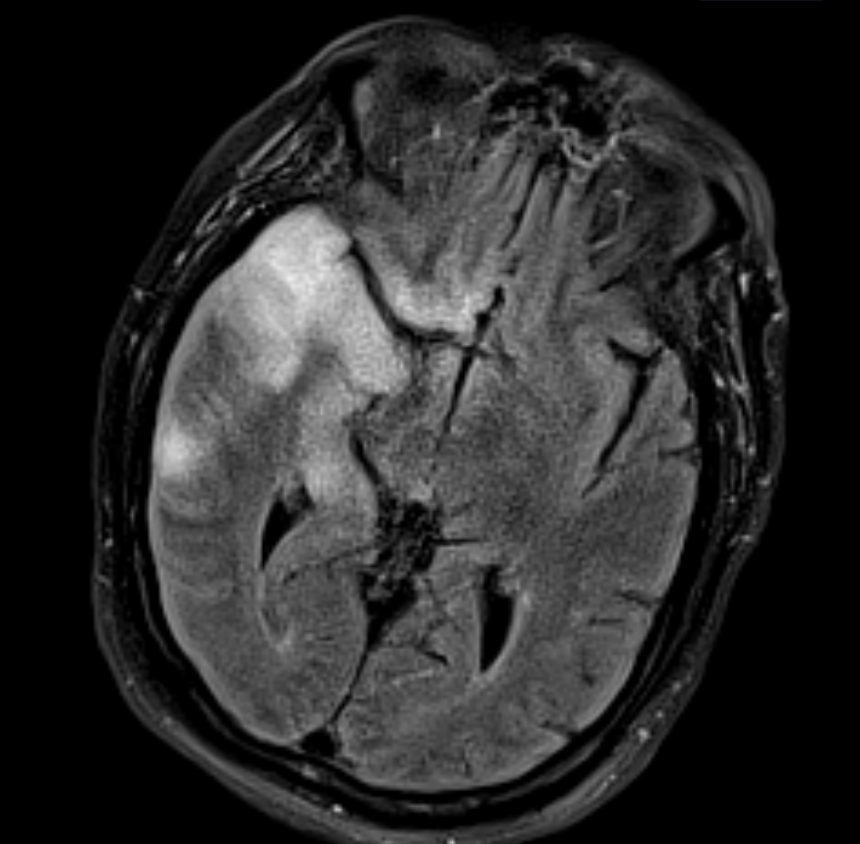

๋‹น์ง ์‹œ ํ”ํžˆ ๋ณผ ์ˆ˜ ์žˆ๋Š” ์‚ฌ๋ก€์˜ ์ „ํ˜•์ ์ธ ์˜ˆ๋ฅผ ํฌํ•จํ•ฉ๋‹ˆ๋‹ค.

39 ์‚ฌ๋ก€

์—ฐ์Šต

๋ฏธ๋ฌ˜ํ•˜๊ฑฐ๋‚˜ ์–ด๋ ค์šด ์‚ฌ๋ก€์™€ ์ผ๋ถ€ ์ •์ƒ ์‚ฌ๋ก€๋ฅผ ํฌํ•จํ•˜์—ฌ ๋‹น์ง์„ ์‹œ๋ฎฌ๋ ˆ์ด์…˜ํ•ฉ๋‹ˆ๋‹ค.

50 ์‚ฌ๋ก€